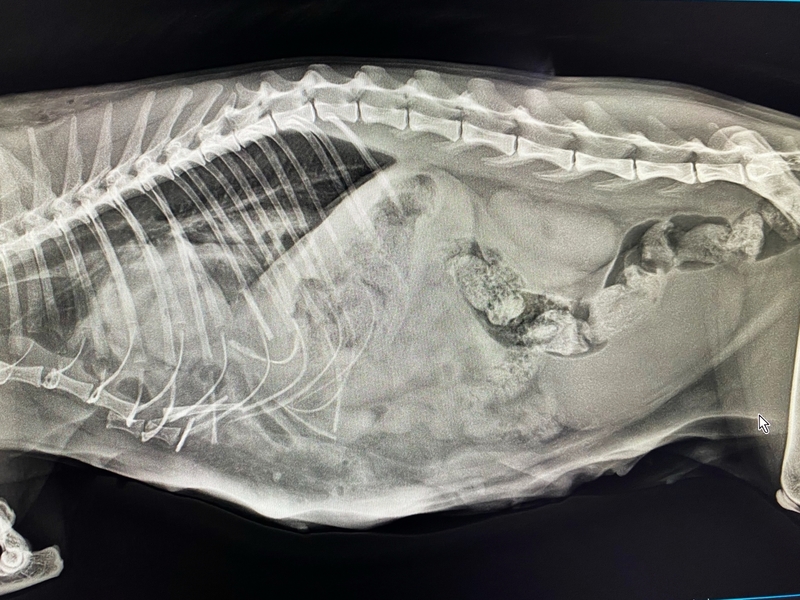

Несчастный случай, травмы и Василиса в Клинике БАРС на приеме неотложной помощи... Проведенная Rg-диагностика показала множественные переломы (один из них - открытый) и значительные внутренние повреждения со смещением органов брюшной полости в грудную клетку. Опытный ветеринарный врач, хирург [club223252442|Анна Сергеевна Кашина] знает, что в таких ситуациях медлить нельзя ни минуты, поэтому она взяла Василису на срочную операцию.

Период восстановления после травматической диафрагмальной грыжи варьируется по времени и зависит от тяжести повреждений внутренних органов, наличия кровотечения и еще ряда факторов. Травмы Василисы были очень серьезными, и, как оказалось в ходе операции, видимые переломы костей - это меньшее из зол. Прогноз был очень осторожным...